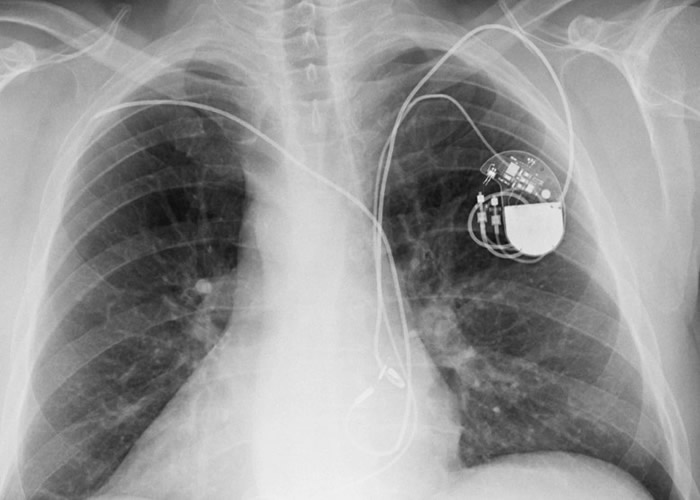

植入式心脏除颤器有机会受黑客攻击。

(蜘蛛网eeook.com报道)美国国土安全部(DHS)日前发表报告,称多达75万个植入式心脏除颤器出现保安漏洞,有机会受黑客攻击。这批器材均由医疗科技公司美敦力(Medtronic)制造,为降低风险,该公司已采取措施监测,并加强网上安全规范。

美媒报道,美敦力所生产的20种产品容易受黑客攻击,包括植入式心脏除颤器。报道指,要操控除颤器或获得使用者数据,不需要太复杂的技术,只要能够进入Conexus遥测系统,就有机会伤害病人。由于该系统缺乏加密功能,也不需身份验证或取得授权,黑客有机会作干扰。